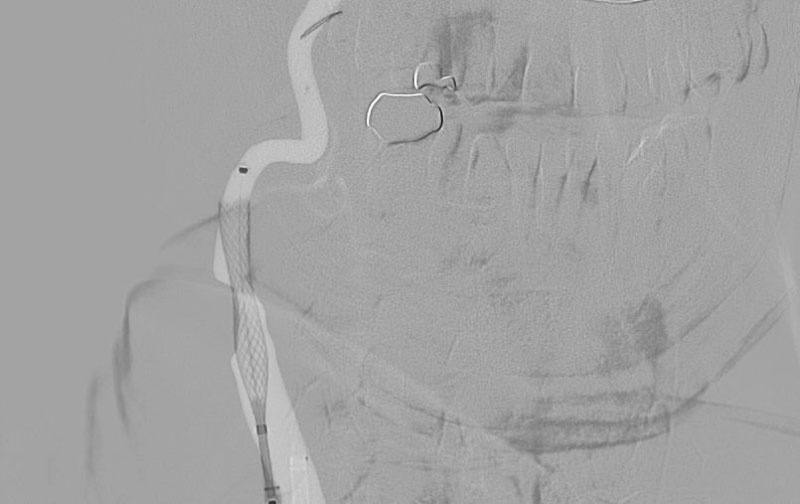

1377

'23年5月17日

右内頚動脈狭窄症

70代

院内外来

中

治療

後

手術日